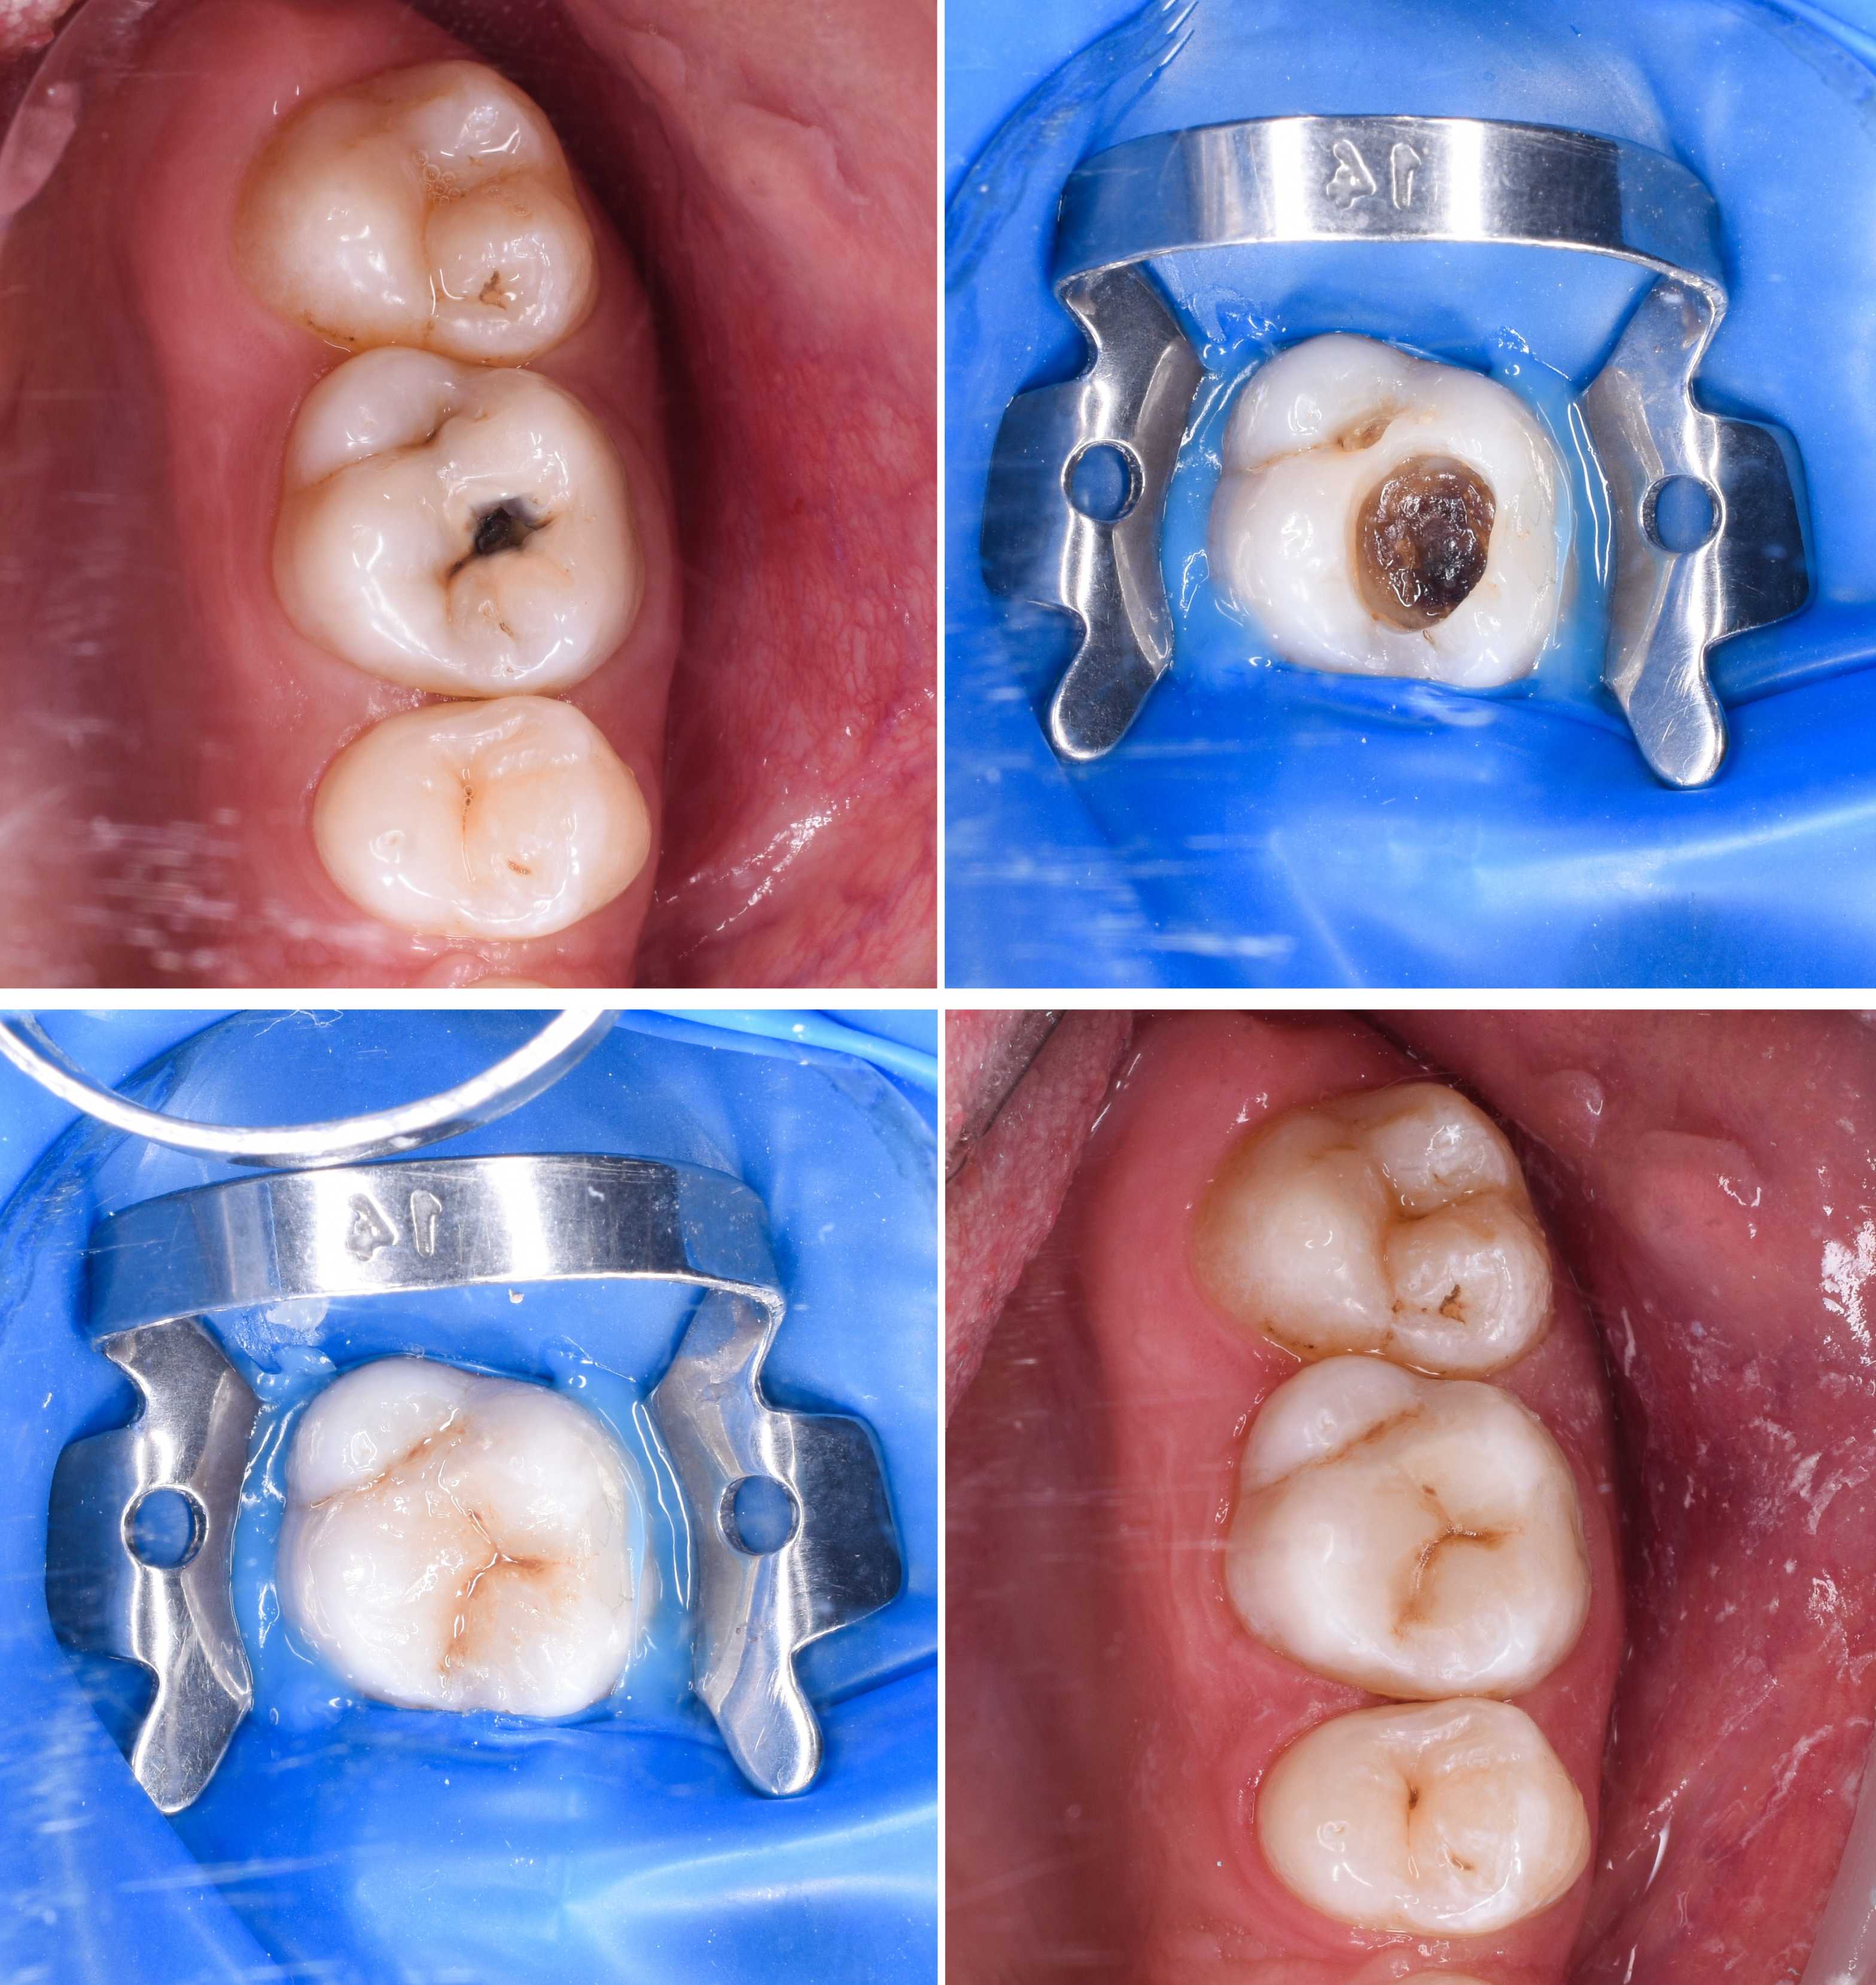

RESTORATIVE DENTISTRY

Are damaged or missing teeth affecting your confidence or oral health? At Credible Dental in Barker Cypress, Houston, TX, we offer a range of restorative dental procedures to repair, replace, and protect teeth. From crowns and bridges to root canal treatment, fillings, inlays, onlays, and dentures, our experienced team is dedicated to restoring the function and beauty of your smile.

• Fillings, Inlays and Onlays

Purpose: We offer composite (tooth-colored) and porcelain fillings to repair cavities and protect teeth from further decay. For more extensive decay that doesn’t require a full crown, we also provide inlays and onlays.

• Inlays: Custom-made to fit within the grooves of the tooth, inlays are used when damage is limited to the center of the tooth.

• Onlays: Also known as partial crowns, onlays extend over one or more cusps, covering a larger area of the tooth.

Procedure: After removing the decayed portion of the tooth, we apply the filling, inlay, or onlay, shaping it to match the natural contours of your teeth for a seamless look and feel.